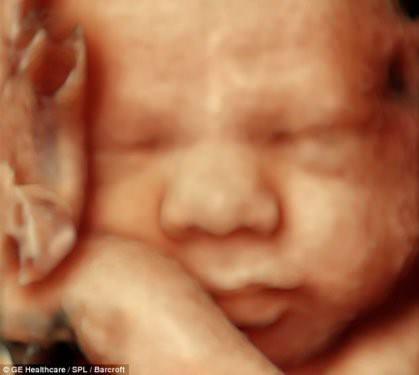

Anne karnında şaşırtan görüntü

Dr Bernard'ın DVD'ye kaydettiği görüntülerde bebeğin rahim içinde tekme atığı sağa sola hareket ettiği, uyuduğu anlaşılırken çok ilgi çeken görüntü ise anne rahmindeki ikiz bebekler oluyor.